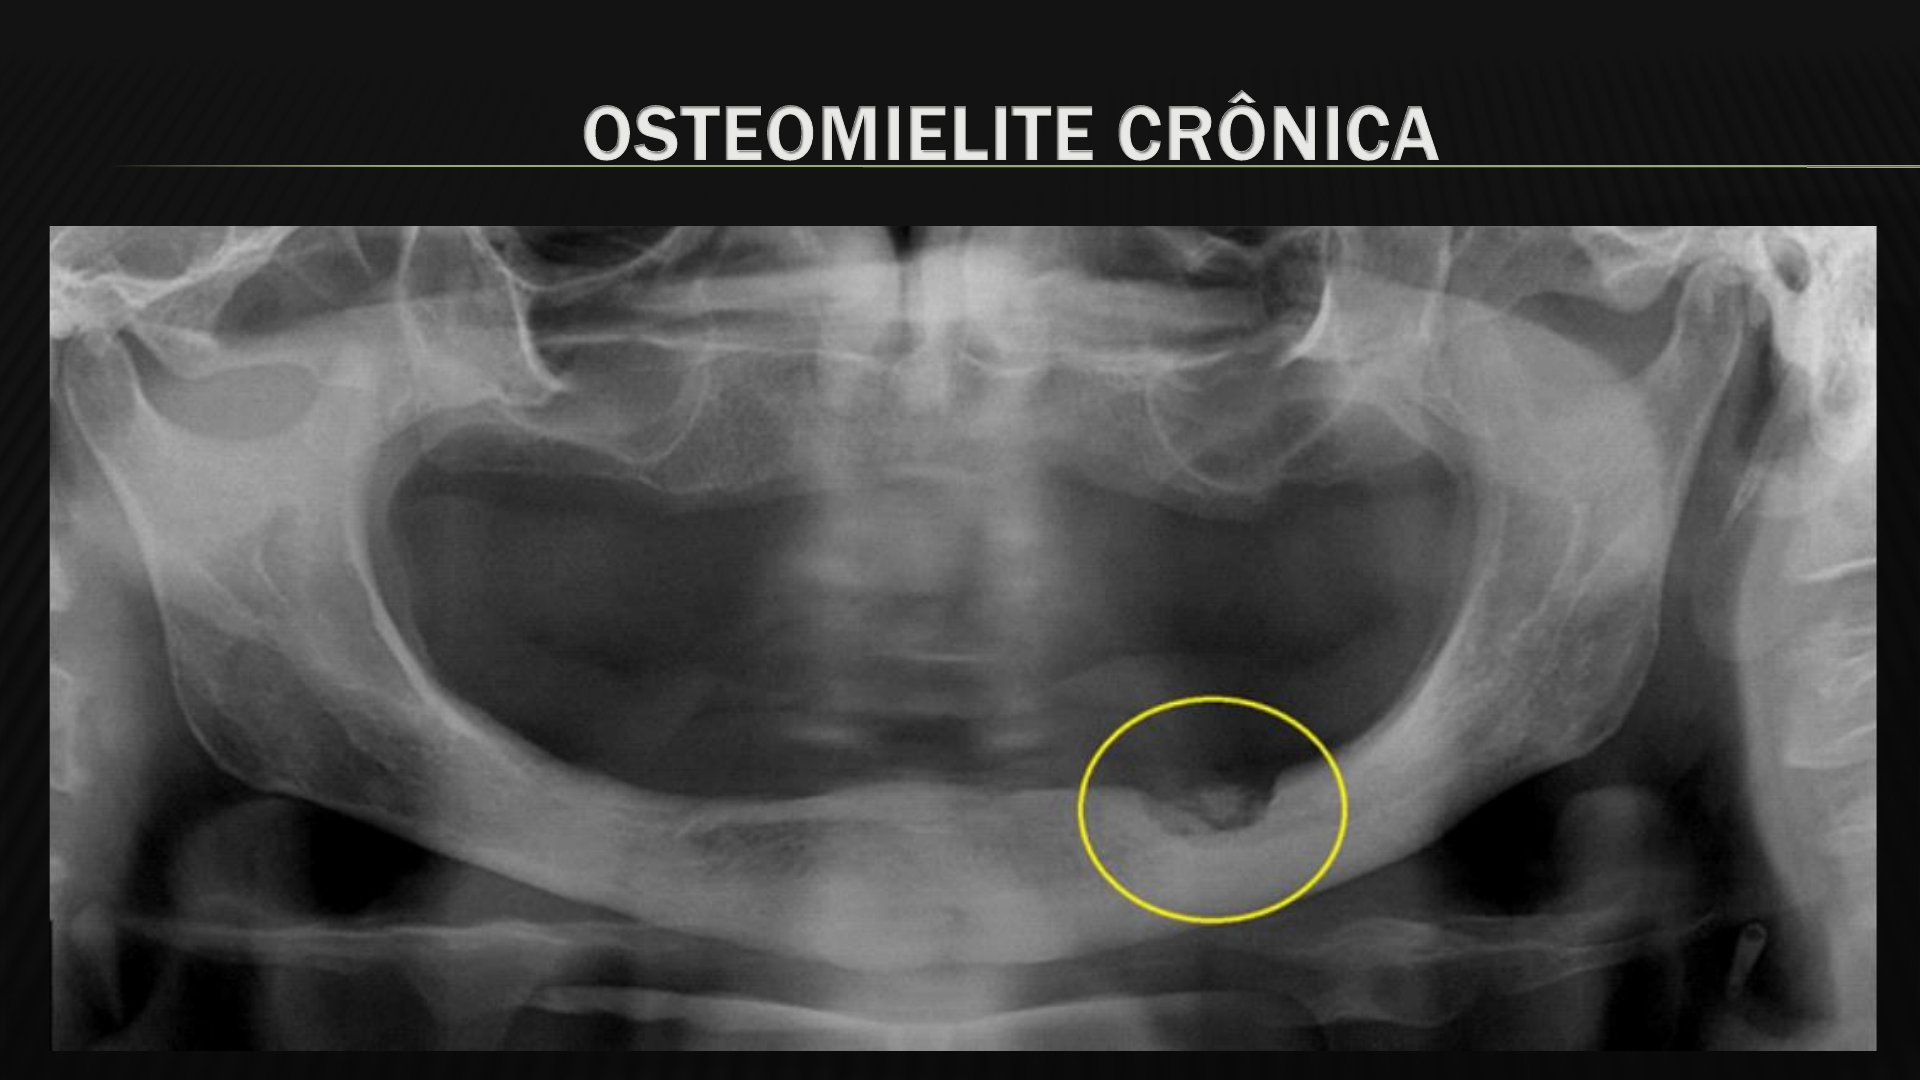

Osteomielitis Crónica Supurativa en Maxilar Superior: Informe de Caso - Studocu